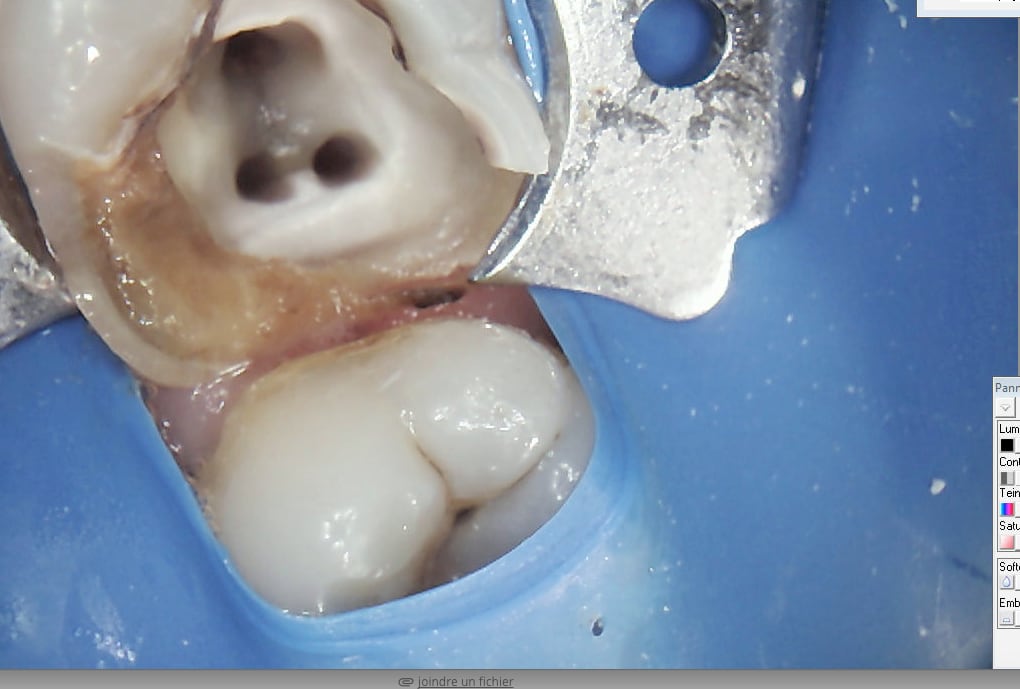

Montre nous des exemples de photos prises en 5s avec ta cam chinoise et compare la avec une photo d une vraie cam.

Avec une bonne cam, tu fais de la localisation des canaux, du controle de taille (distal de la 7 du haut) et communication avec le protho (personnalisation des ceram, maquillage des sillons)

C'est évident qu'il y a pas photo (si j'ose dire) qu'une vraie cam est meilleure, mais tout dépend de l'utilisation que tu en fais.